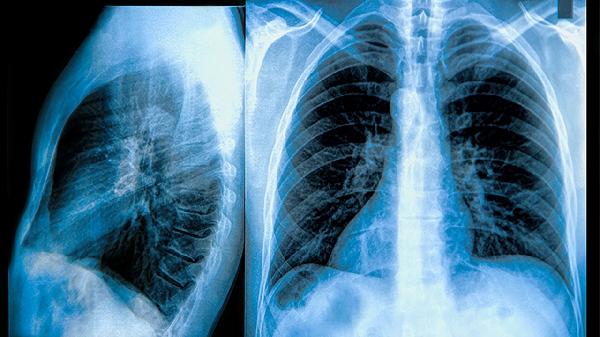

3、良性病变如肝硬化、肺纤维化等同样可能导致癌胚抗原偏高。这些疾病引起的组织损伤会释放癌胚抗原。治疗需针对原发病,如肝硬化患者需戒酒并服用保肝药物,肺纤维化可使用免疫抑制剂。